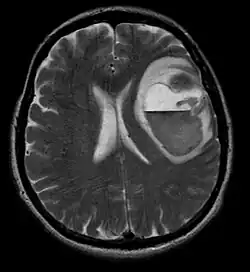

A tomografia computadorizada (TC) e a ressonância magnética (RM) podem detectar efetivamente uma neoplasia no cérebro. A RM é mais sensível que a TC para identificar lesões, mas contraindicações para pacientes com marcapasso cardíaco, próteses incompatíveis, clipes metálicos e outros. A TC continua sendo o método de escolha para detectar calcificações dentro de lesões ou erosões ósseas da calota craniana ou da base. A utilização de agentes de contraste, que são iodados no caso da TC e paramagnéticos ( gadolínio ) no caso da RM, permite a aquisição de informações sobre a vascularização e integridade da barreira hematoencefálica, uma melhor definição do tumor tumoral comparado ao edema circundante e à geração de hipóteses sobre o grau de malignidade . O exame radiológico também permite avaliar os efeitos mecânicos e consequentes alterações nas estruturas cerebrais decorrentes do tumor, como hidrocefalia e hérnias, cujos efeitos podem ser fatais. Finalmente, na preparação para a cirurgia, esse diagnóstico pode ser usado para determinar a localização da lesão ou a infiltração do tumor em áreas vitais do cérebro. Para isso, a RM é mais eficiente que a TC, pois pode fornecer imagens tridimensionais.

As ferramentas de diagnóstico por imagem radiológica destacam a mudança no tecido neoplásico em comparação com o parênquima cerebral normal (através de alterações na densidade do tecido fotografado eletronicamente na TC e na intensidade do sinal na RM). Como a maioria dos tecidos patológicos, os tumores também são reconhecidos por um acúmulo aumentado de água intracelular. Na tomografia computadorizada aparecem hipodensa, ou seja, de menor densidade que o parênquima cerebral, na tomografia de ressonância magnética nuclear com relaxamento spin-lattice T 1 hipointenso e em relaxamento spin-spin T 2 bem como a ponderação de prótons (PD) hiperintensa.

A tomografia computadorizada do cérebro normalmente mostra uma massa de tecido que pode ser realçada por qualquer contraste. Na TC, os gliomas de baixo grau geralmente parecem isodensos ao parênquima normal e, portanto, podem não apresentar realce pelo contraste. Da mesma forma, lesões na fossa posterior do crânio são difíceis de identificar na TC. Consequentemente, os resultados dessa tomografia isoladamente nem sempre são suficientes para fins diagnósticos. Em casos duvidosos, o uso da ressonância magnética mais sensível é essencial.

Na ressonância magnética, um tumor intracraniano aparece como uma lesão maciça que pode se tornar mais luminescente após o uso do agente de contraste. No entanto, há sempre uma anomalia de sinal na ressonância magnética, que indica a presença de neoplasia ou edema vasogênico. Normalmente, o aumento da luminescência (realce pelo contraste) é indicativo de um tumor de grau mais alto de malignidade. Um anel contrastante é característico do glioblastoma, com a porção luminescente correspondendo à parte vital do tumor maligno e a área mais escura-hipointense à necrose tecidual.